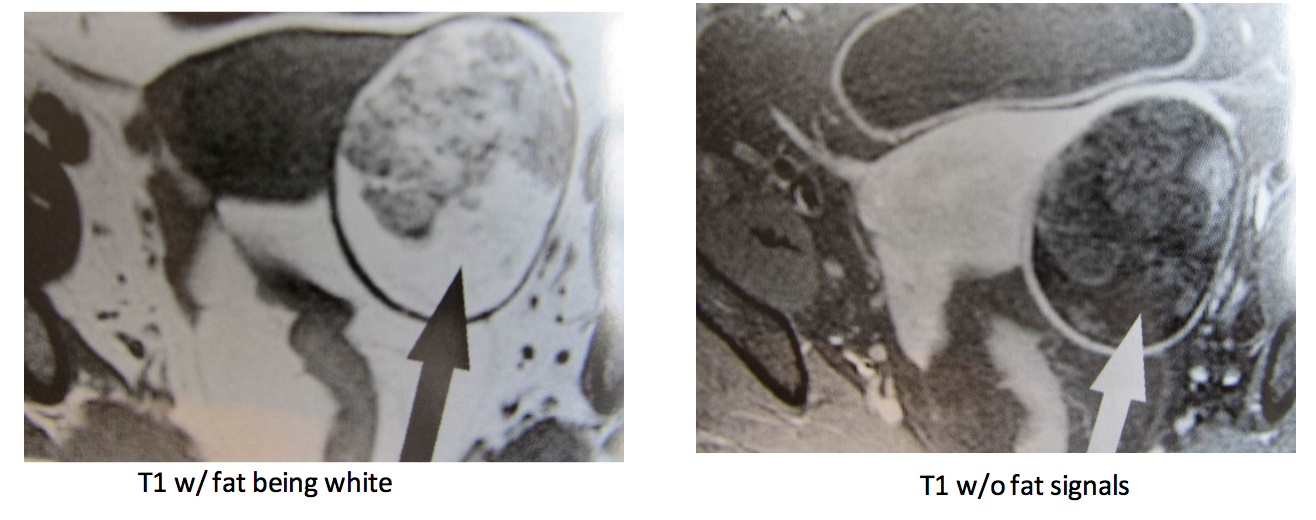

What this be?

Dermoid (mature cystic teratoma) - presence of fat